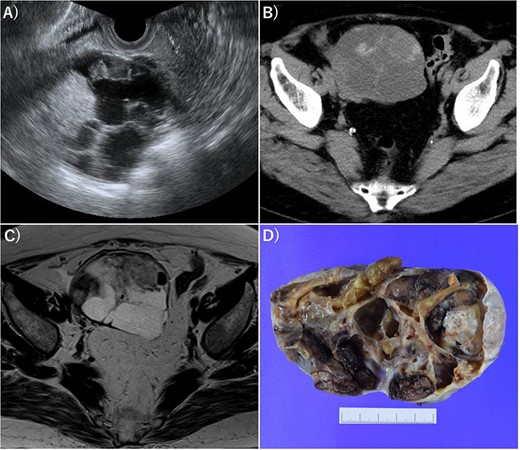

Imaging of OG. (A) Transvaginal ultrasonography showed numerous separate structures and substantial nodules. (B) CT showed a 10.5-cm multifocal cystic tumor on the right side of the uterus. (C) Magnetic resonance imaging (T2-weighted image) revealed a tumor with numerous separate structures and substantial nodules, which led to speculations that the cystic area was serous. Right ovarian cancer was suspected. (D) Gross examination also showed numerous separate structures and substantial nodules.